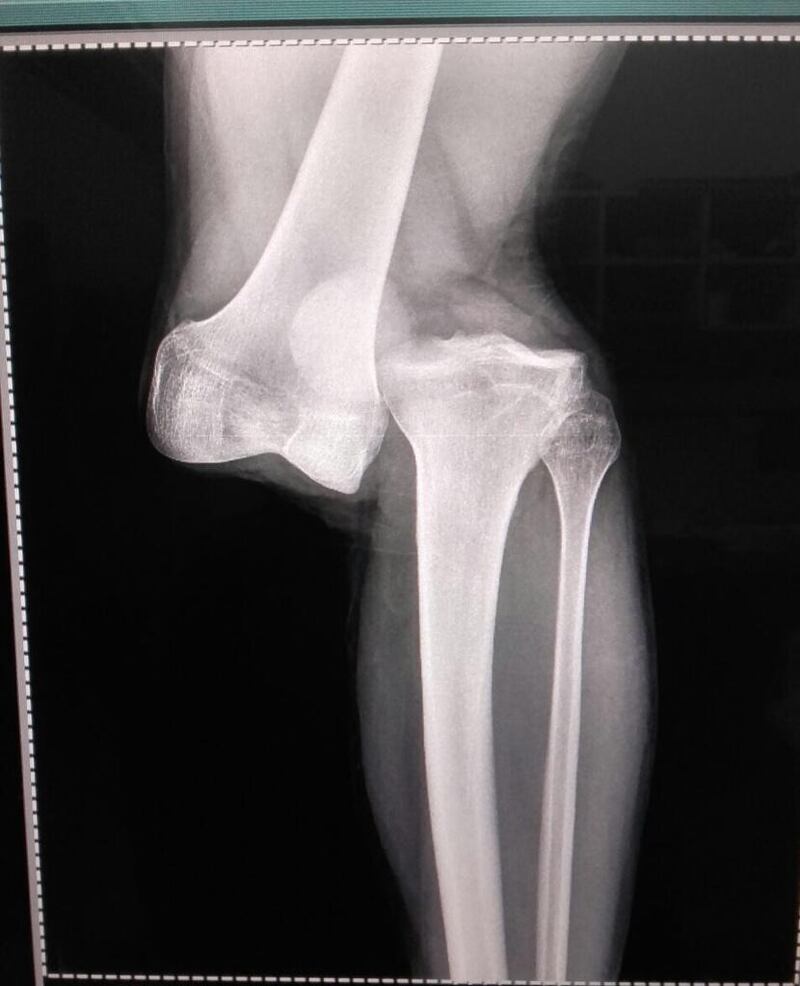

“En 23 años como médico nunca vi una lesión así. Es casi una separación del fémur y el peroné. Hay rotura de cruzado, anterior, posterior... Hay que hacer una reconstrucción. La recuperación es de entre 10 y 12 meses”, sentenció el galeno a D Sport Radio.

Adicional, señaló que “hay que hacer una reconstrucción (quirúrgica). La recuperación es de entre 10 y 12 meses”.